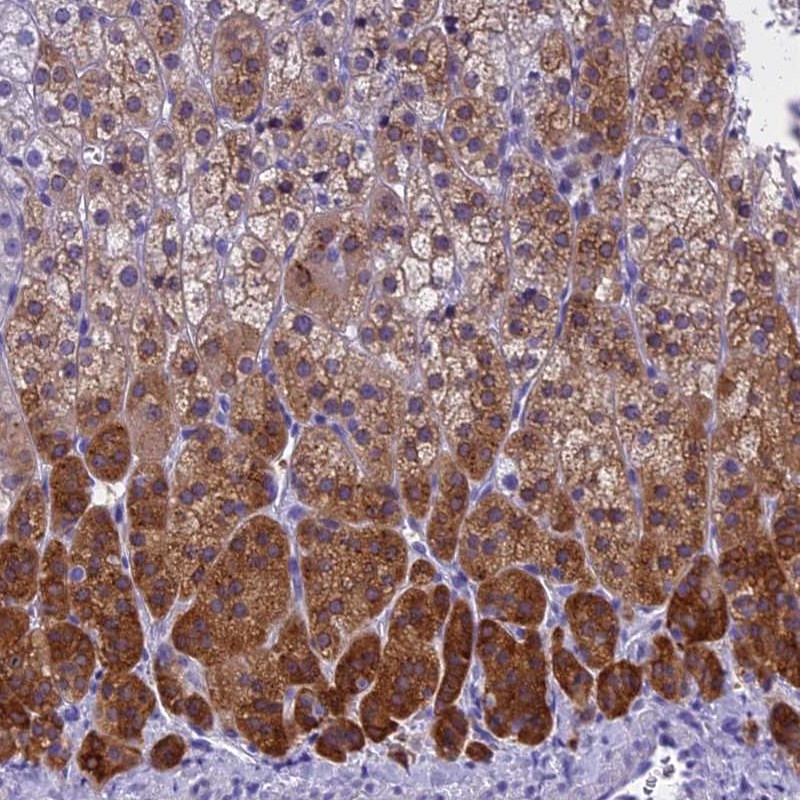

Immunohistochemistry analysis in human adrenal gland and skeletal muscle tissues using Anti-KCTD14 antibody. Corresponding KCTD14 RNA-seq data are presented for the same tissues.